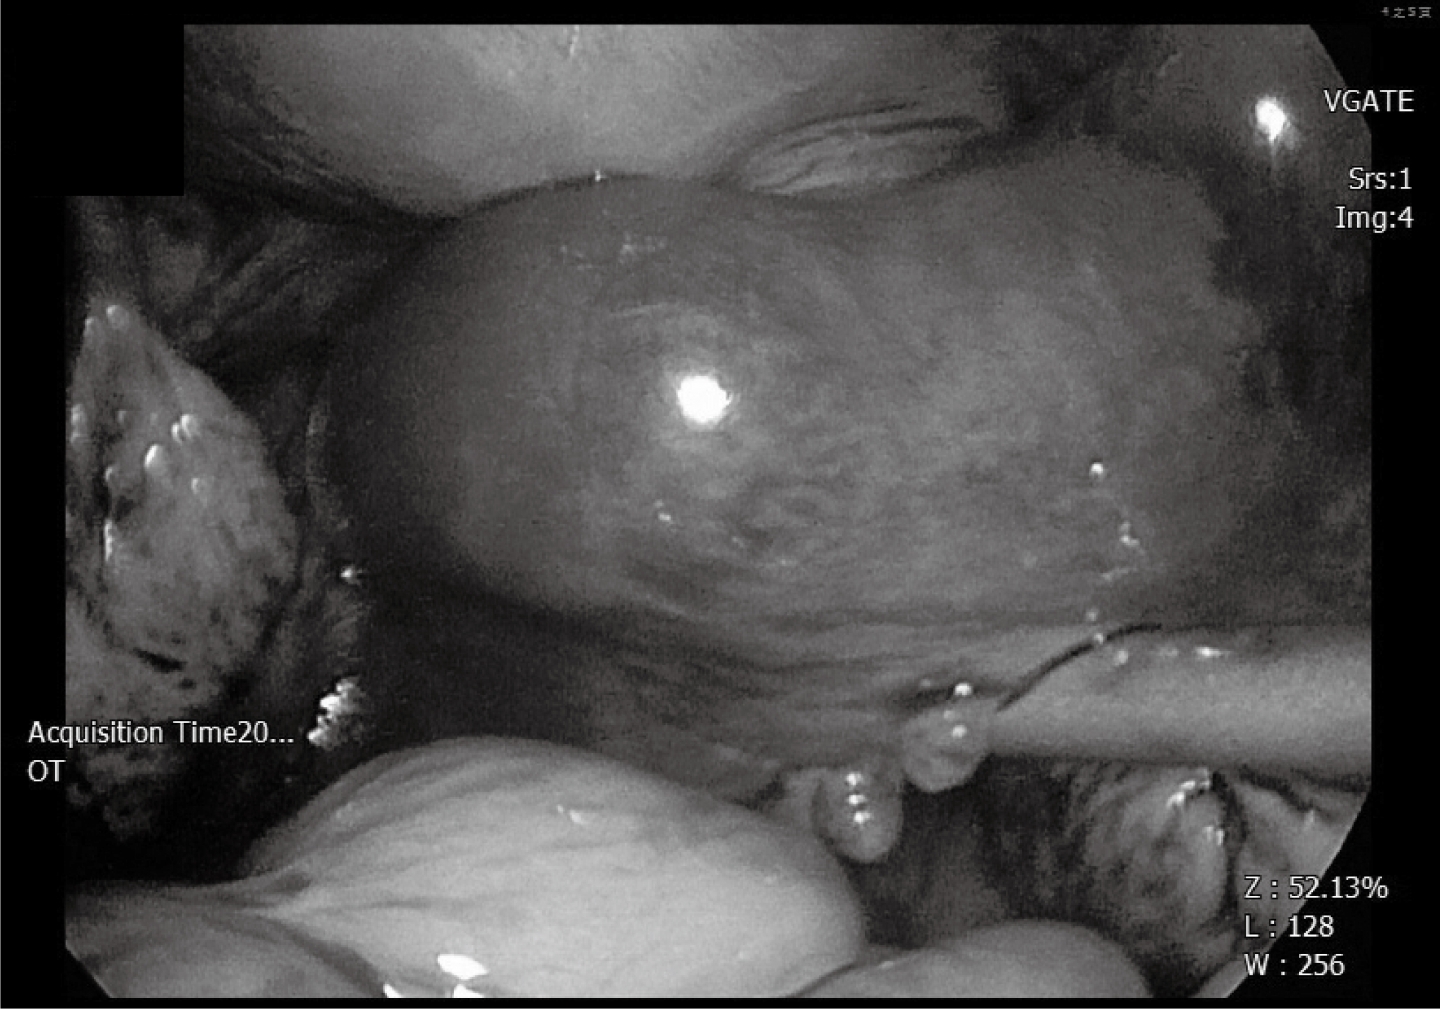

經解釋後,這對夫妻不想接受試管嬰兒治療,於是選擇人工受孕,在吃排卵藥物的那個月,還來不及使用藥物就發現自己懷孕了,更令人驚訝的是,這次是右邊輸卵管的子宮外孕。這次子宮外孕,她堅決要保留輸卵管,我們採用腹腔鏡注射藥物的方式來治療子宮外孕。 開刀的當下看見腫脹的右側輸卵管,我陷入天人交戰 「天啊!這麼肥的輸卵管留下來有用嗎?」 一陣擔心之餘還是依照患者決定,使用保留輸卵管子宮外孕的治療方式。

(肥厚的輸卵管圖-示意畫面)

(當然後續超音波追蹤時,我還是非常擔心這個輸卵管能用嗎?)